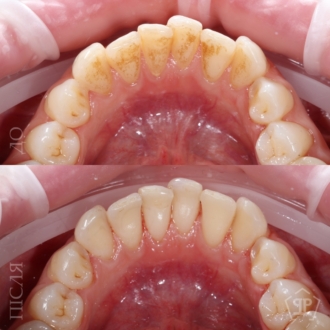

Комплексная гигиена зубов: гигиеническая чистка скейлером + аппаратом Air-Flow + полировка зубов профессиональной пастой